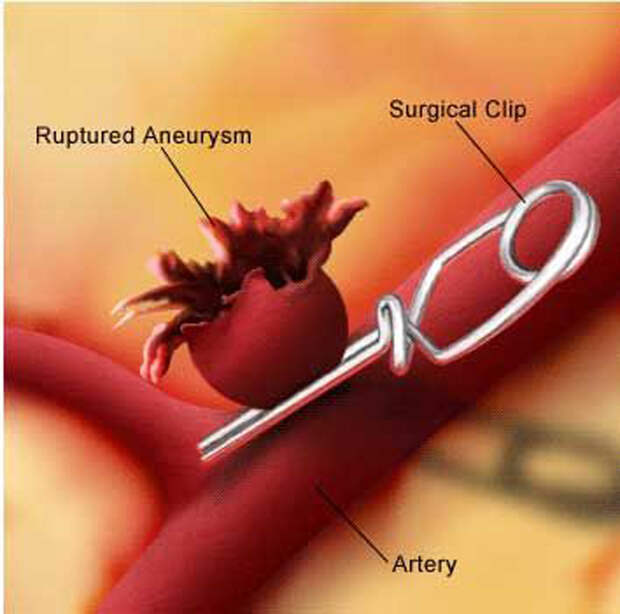

Снимки и иллюстрации микроаневризм сосудов головного мозга